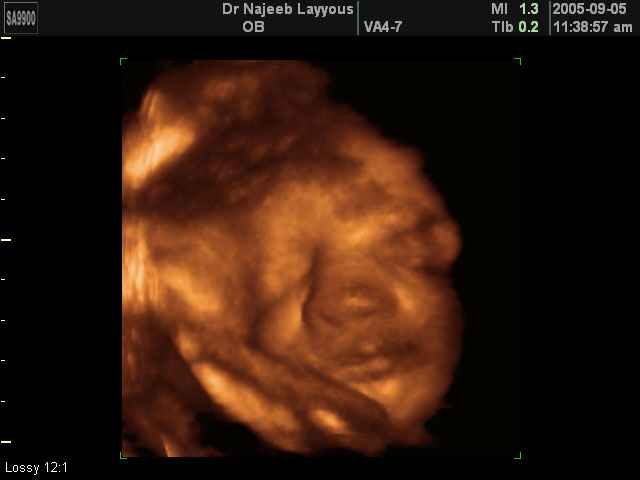

صور لوجه الجنين بجهاز الالتراساوند ثلاثي الأبعاد | الدكتور نجيب ليوس

صور لوجه الجنين بجهاز الموجات فوق صوتية ثلاثي الأبعاد